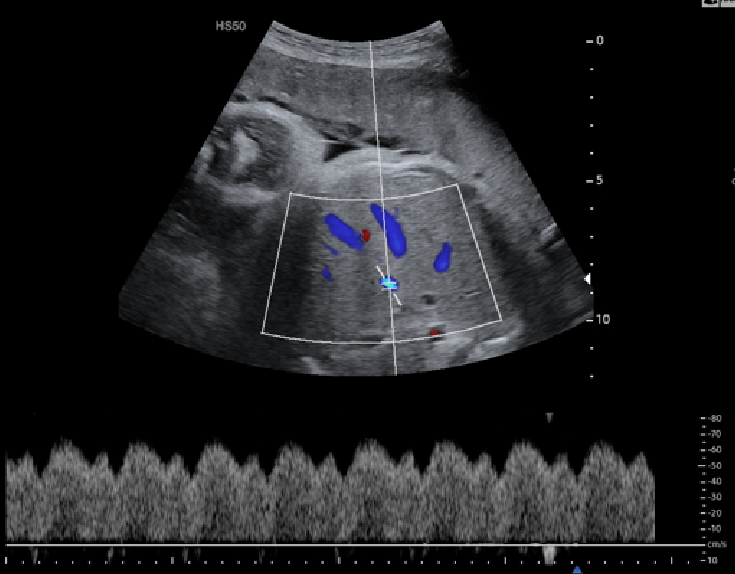

Doppler Μέσης Εγκεφαλικής Αρτηρίας

Η Υπερηχογραφία Doppler της Μέσης Εγκεφαλικής Αρτηρίας ενδείκνυται σε δυο περιπτώσεις:

- Παρακολούθηση κυήσεων με εμβρυική αναιμία.

- Παρακολούθηση κυήσεων με παθολογικό εύρημα στην Ομφαλική Αρτηρία

Εικόνα 04 - Φυσιολογική καμπύλη Doppler Μέσης Εγκεφαλικής Αρτηρίας